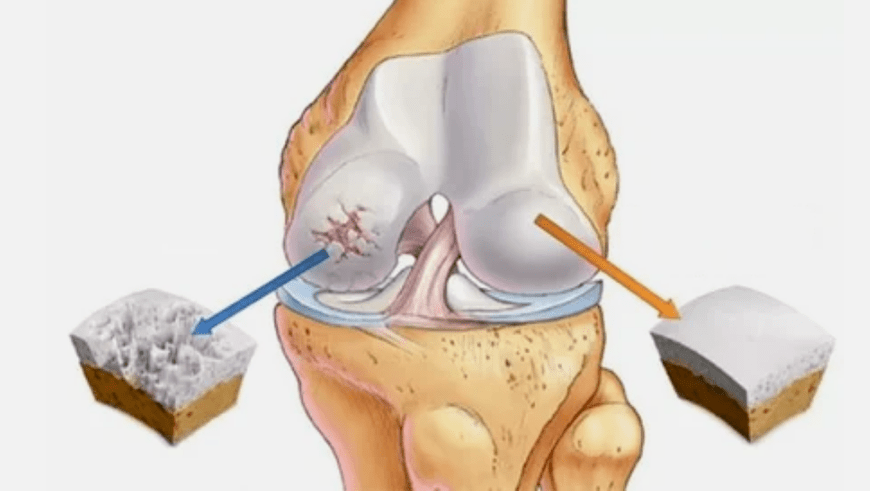

- La lesión primaria afecta el cartílago hialino. En caso de trastornos circulatorios, se produce el deterioro del poder patológico. Es el primer paso o causa, que puede ocurrir artrosis.

- Patologías de recubrimiento de Hyalin. El adelgazamiento del cartílago conduce al reemplazo de sus tejidos patológicos: estructuras óseas.

- Los crecimientos anómalos aparecen en el cartílago - osteófitas.

- La violación de la anatomía natural del cartílago y los huesos provoca la sobrecarga de áreas saludables de cartílago. La destrucción de tejidos articulares sin tratamiento progresa constantemente y conduce a discapacidad.

Cuando aumenta el grado de enfermedad, los procesos patológicos aún se agravan. Al final, todo el cartílago de Hyalin se destruye.